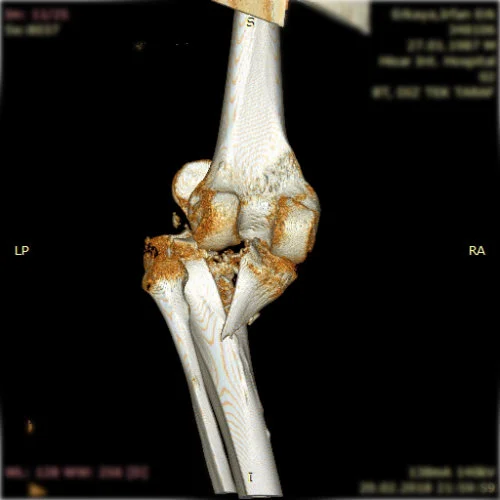

Görüntüleri büyütmek için resmin üstüne tıklayınız.